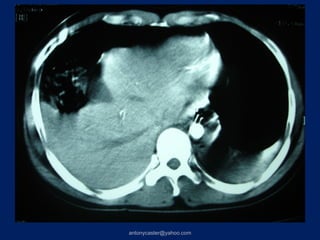

TRAUMA TÓRACO- ABDOMINAL         2da TC:(8 días después)   3raTC: ( 41 días

1ra TC: 28:07:04                             después)

IV

VIII

VII

> 3 Couinaud’s AIS90-5            HEMATOMA SUBCAPSULAR

Complicación= Biloma

V

VI

TRAUMA TÓRACO- ABDOMINAL 2da TC:(8 días después) 3raTC: ( 41 días 1ra TC: 28:07:04 después) IV VIII VII > 3 Couinaud’s AIS90-5 HEMATOMA SUBCAPSULAR Complicación= Biloma IV V VI